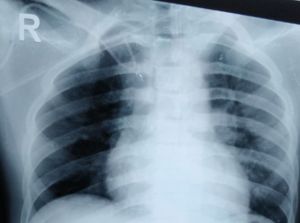

Post procedure xray of lt subclavian cvp line insertion.. Is it misplaced? Does it need repositioning?

Definitely. It is curled in the axial